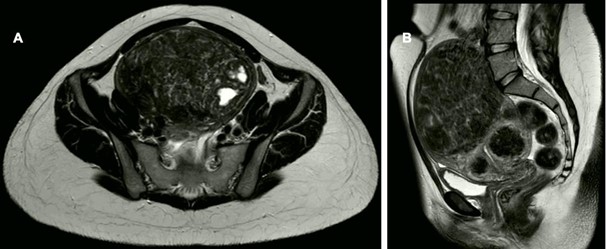

Further imaging via MRI delineated a 16 x 10 x 13 cm enlarged uterus with a 12 cm lesion displaying signal intensity akin to myometrial tissue, consistent with a uterine leiomyoma. Two additional smaller leiomyomas were identified in the lower uterine segment, with no evidence of infiltrative growth. The larger leiomyoma exhibited signs of necrosis. No pathological lymphadenopathy or adjacent organ infiltration was observed.

Figure 1: Radiologic findings in the 1st case. Large uterine fibroid (uterus myomatosus) without signs of infiltration. No pathological lymph nodes. Bilateral cystic ovaries.